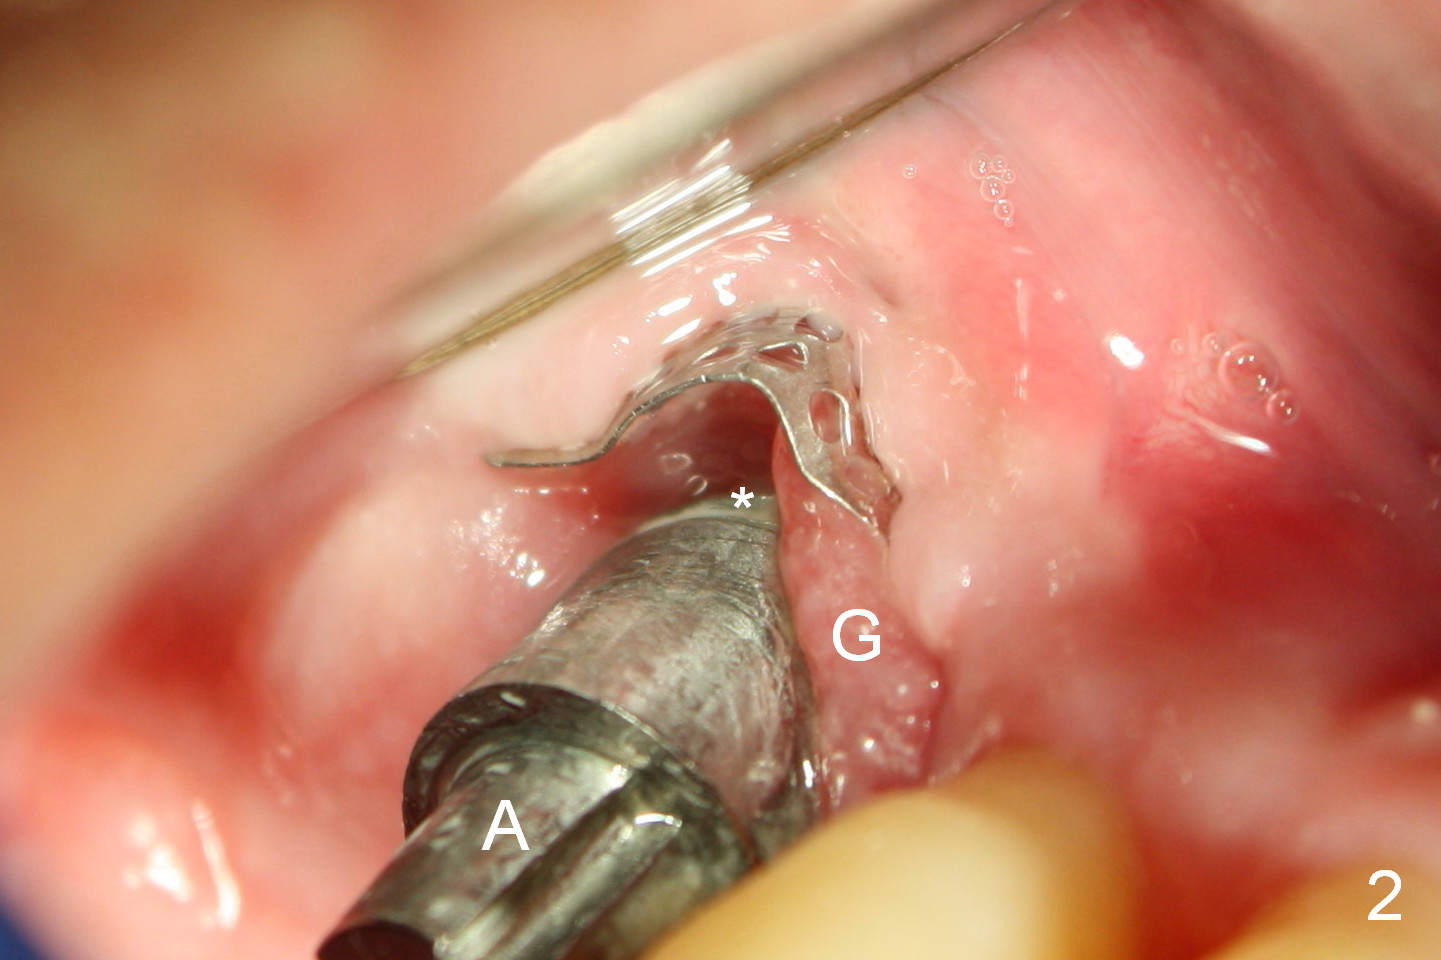

When he returns 1 month postop, the Titanium mesh is exposed asymptomatically (Fig.2). The implant threads appear not to be exposed. When to remove the mesh? A: abutment, which is removed before discharge of the patient. G: granulation tissue; *: possible the rough (R) surface of the implant (S: smooth surface).